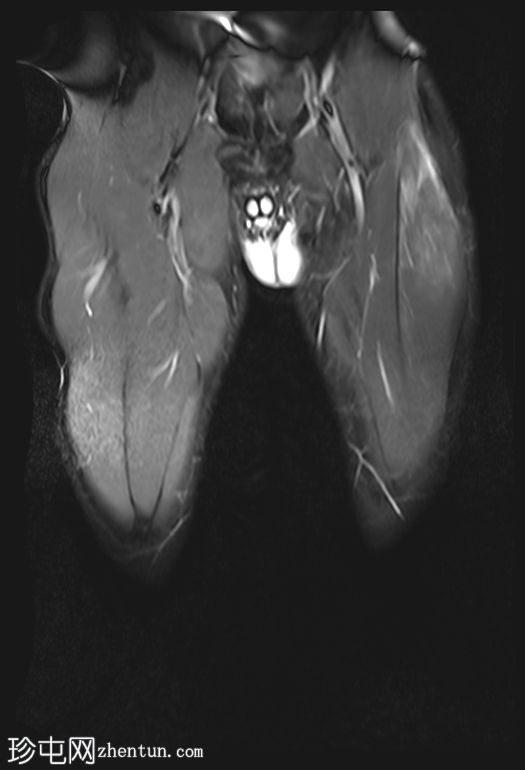

矢状位

T1加权像

股直肌近端和中段前外侧可见一水肿性高信号影,长约15厘米,宽约3厘米。肌纤维轻度分离,但未见撕裂。肌内未见积液;在相邻肌间隙可见一条细小的液线环绕肌肉,延伸至近端肌腱交界处。

股直肌中段的间接肌腱轻度增厚,伴有肌腱周围水肿,提示2B级拉伤。但肌腱保持连续性,骨性附着良好,未见撕裂。